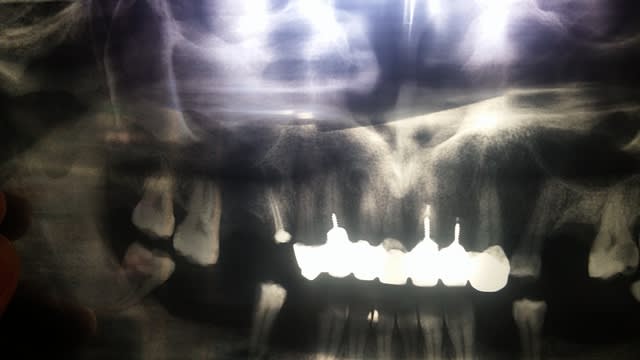

Un patient voudrait refaire son bridge sup car pas très esthétique... Moi j'ai direct reniflé le bon plan!

Je lui demande quand même d'aller faire une pano pour avoir une idée globale des fondations, et c'est le drame.

Bridge réalisé il y a 2-3 années dans son pays d'origine.

Franchement je sais pas par ou commencer?

Oui je vois, mais est ce qu'avec une endo dans les règles 12, 13 et 14 vont s'en sortir?

Ou résection/curetage indispensable?

J'ai déjà viré la 15, et la 16 c’était la semaine dernière.

Aussi, est ce que l'autre prat était inconscient, ou c'est quoi cette technique d'ancrage sans obturation canalaire...?

P.S en regardant a nouveau la pano ... tu peux commencer par lui faire l'endo sur la 27 bien dans les régles et voir comment il réagit car a l'evidence personne n'a jamais passé plus de 10 min sur une endo, meme pas sur qu'on lui ai mis de l'hypochlorite une fois dans sa vie, donc un rincage a chaque instrument ca va le surprendre et :